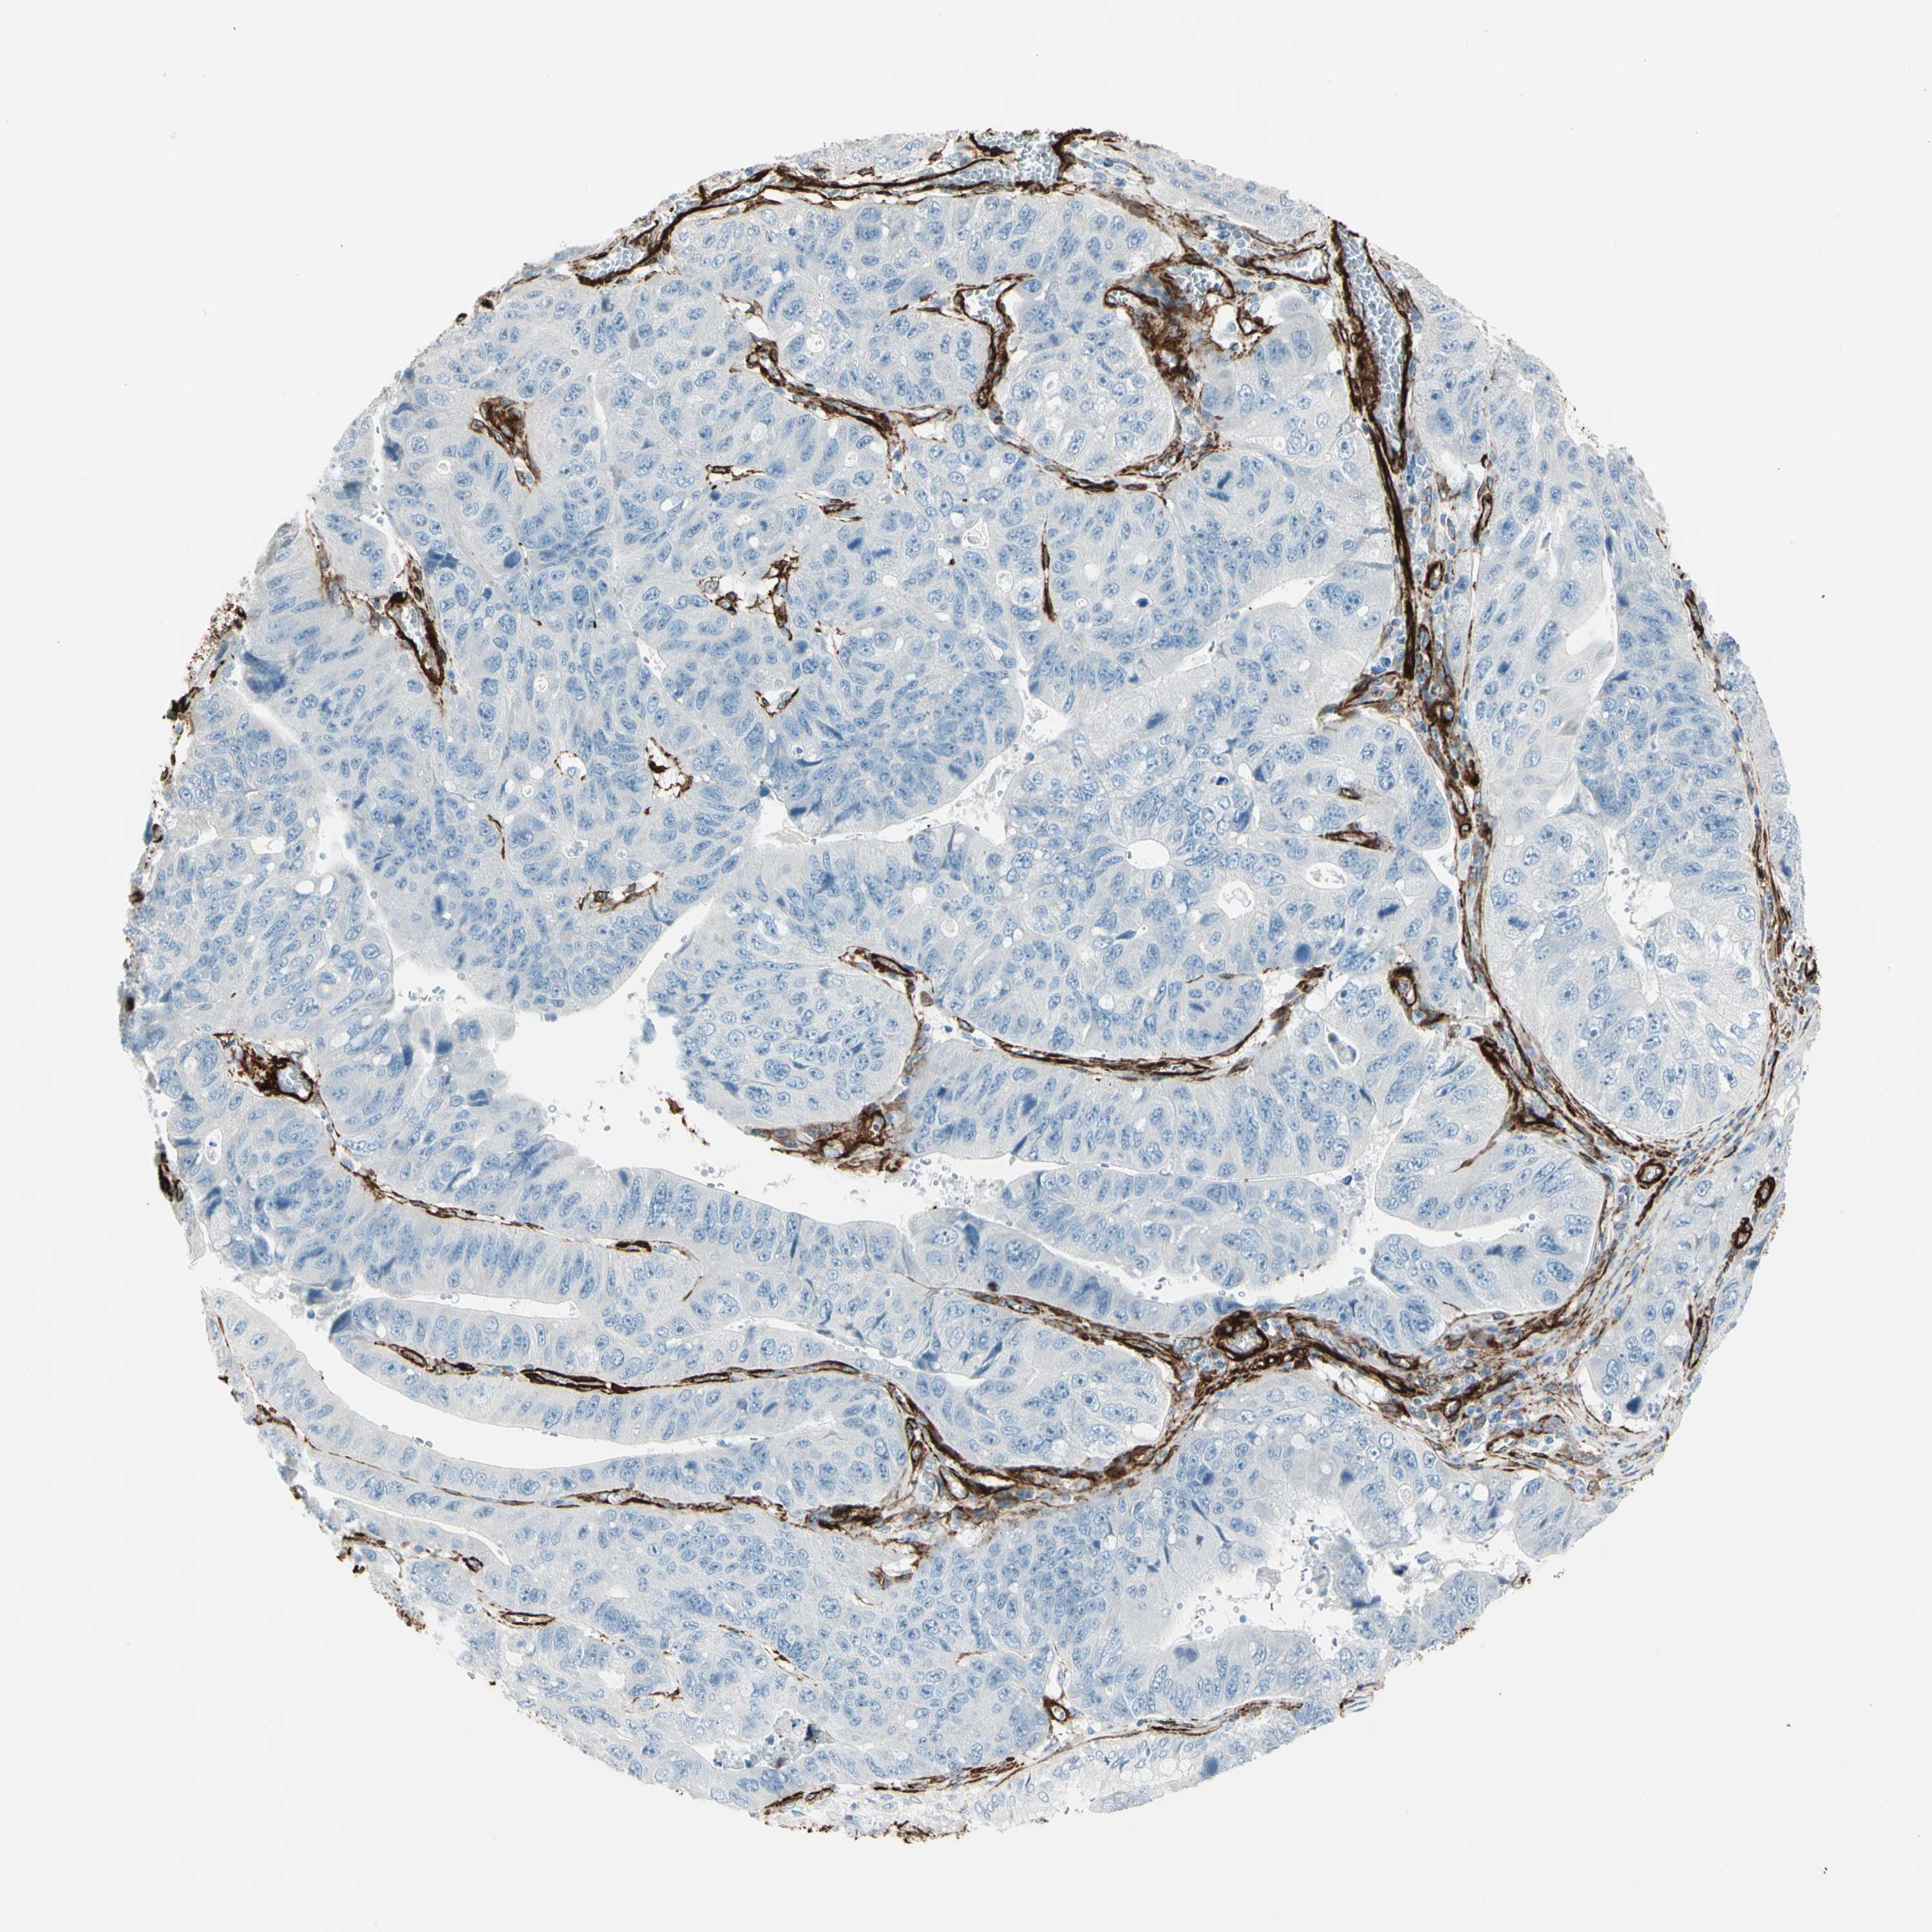

STOMACH CANCER - Protein expressioni

A mouse-over function shows sample information and annotation data. Click on an image to view it in a full screen mode. Samples can be filtered based on level of antibody staining by selecting one or several of the following categories: high, medium, low and not detected. The assay and annotation is described here.

Note that samples used for immunohistochemistry by the Human Protein Atlas do not correspond to samples in the TCGA dataset.

Antibody stainingi

Antibody staining in the annotated cell types in the current human tissue is reported as not detected, low, medium, or high, based on conventional immunohistochemistry profiling in selected tissues. This score is based on the combination of the staining intensity and fraction of stained cells.

Each image is clickable and will lead to virtual microscopy that enables deeper exploration of all samples and also displays staining intensity scores, fraction scores and subcellular localization as well as patient and tissue information for each sample.

Antibody HPA008066

Antibody HPA017330

Antibody CAB000006

Staining

High

Medium

Low

Not detected

Intensity

Strong

Moderate

Weak

Negative

Quantity

>75%

75%-25%

<25%

None

Location

Nuclear

Cytoplasmic/membranous

Cytoplasmic/membranous,nuclear

Adenocarcinoma, NOS